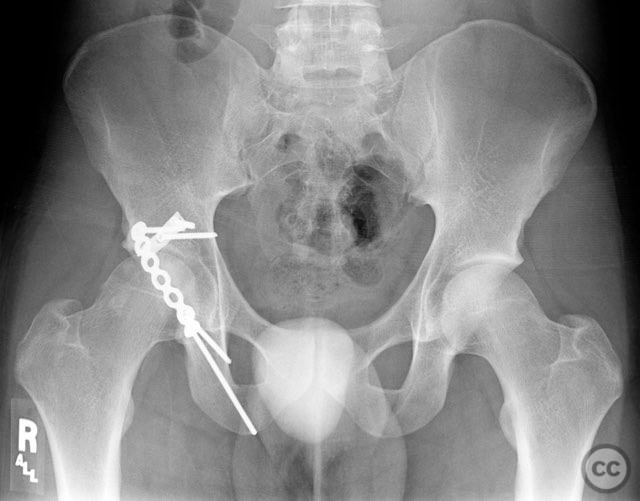

Clinical and radiological findings:  A 20-year-old male collegiate basketball player sustained a displaced right posterior wall (PW) acetabular fracture-dislocation during practice. Initial AP pelvic radiograph demonstrated a reduced femoral head with a displaced posterior wall fragment. Axial CT imaging revealed a large, peripherally located PW fragment with significant displacement, impaction into the abductor muscle mass, and no intra-articular comminution. Obturator oblique radiographs and intraoperative fluoroscopy under anesthesia demonstrated mechanical obstruction to passive abduction at 10–20 degrees due to the relationship between the displaced PW fragment and the greater trochanter.

Intraoperatively, the posterior wall fragment was found firmly embedded within the abductor musculature, necessitating careful disimpaction and minimal periosteal stripping to preserve vascularity. The spring-hook device provided secure capture of the peripheral fragment without involving the labrum. Placement of the reconstruction plate medial to the hook tines provided buttress support to prevent secondary displacement. Fluoroscopic imaging confirmed anatomic reduction and extra-articular screw placement. Postoperative CT demonstrated satisfactory reduction and implant positioning.

Orthopaedic implants used:   Spring-hook acetabular fixation device; 3.5 mm reconstruction plate; cortical screws (extra-articular).